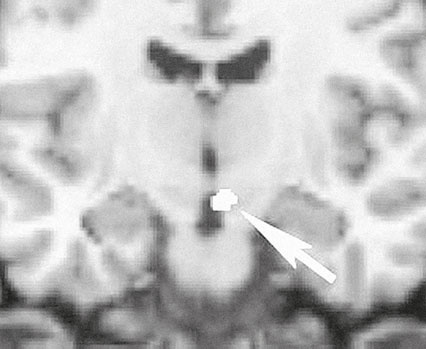

Сходство реакций на любимую картину, любимого человека и наркотические вещества, вызывающие зависимость, впервые продемонстрировали Люси Браун, Хелен Фишер и их коллеги из Медицинского колледжа им. А. Эйнтшейна и Ратгерского университета. Эти ученые продолжили исследования Семира Зеки, посвященные воздействию картин на зрителя. Испытуемыми в их экспериментах стали люди, недавно влюбившиеся, и люди, недавно отвергнутые возлюбленными. Реакции тех и других на изображения возлюбленных включали и активацию нейронов орбитофронтальной коры, и активацию дофаминергической системы (рис. 23–2), которая играет ключевую роль в положительном подкреплении, связанном с ожиданием и получением награды (гл. 26). Причем у тех отвергнутых, кто был по-прежнему влюблен, система награды активировалась даже сильнее, чем у счастливых влюбленных. Таким образом, влюбленность представляется своего рода естественной зависимостью, в которой задействована система мотивации, связанная со стремлением к награде, и более похожей на такие явления как голод, жажда или ломка, чем на эмоциональные состояния. Вероятно, этим и объясняется усиление чувств, возникающее, когда влюбленный лишается возможности видеть дорогое ему изображение, как это было с Лаудером и климтовским портретом.

Рис. 23–2. Когда испытуемые смотрели на изображения возлюбленных, у них в мозге возбуждались дофаминергические нейроны вентральной области покрышки правого полушария.